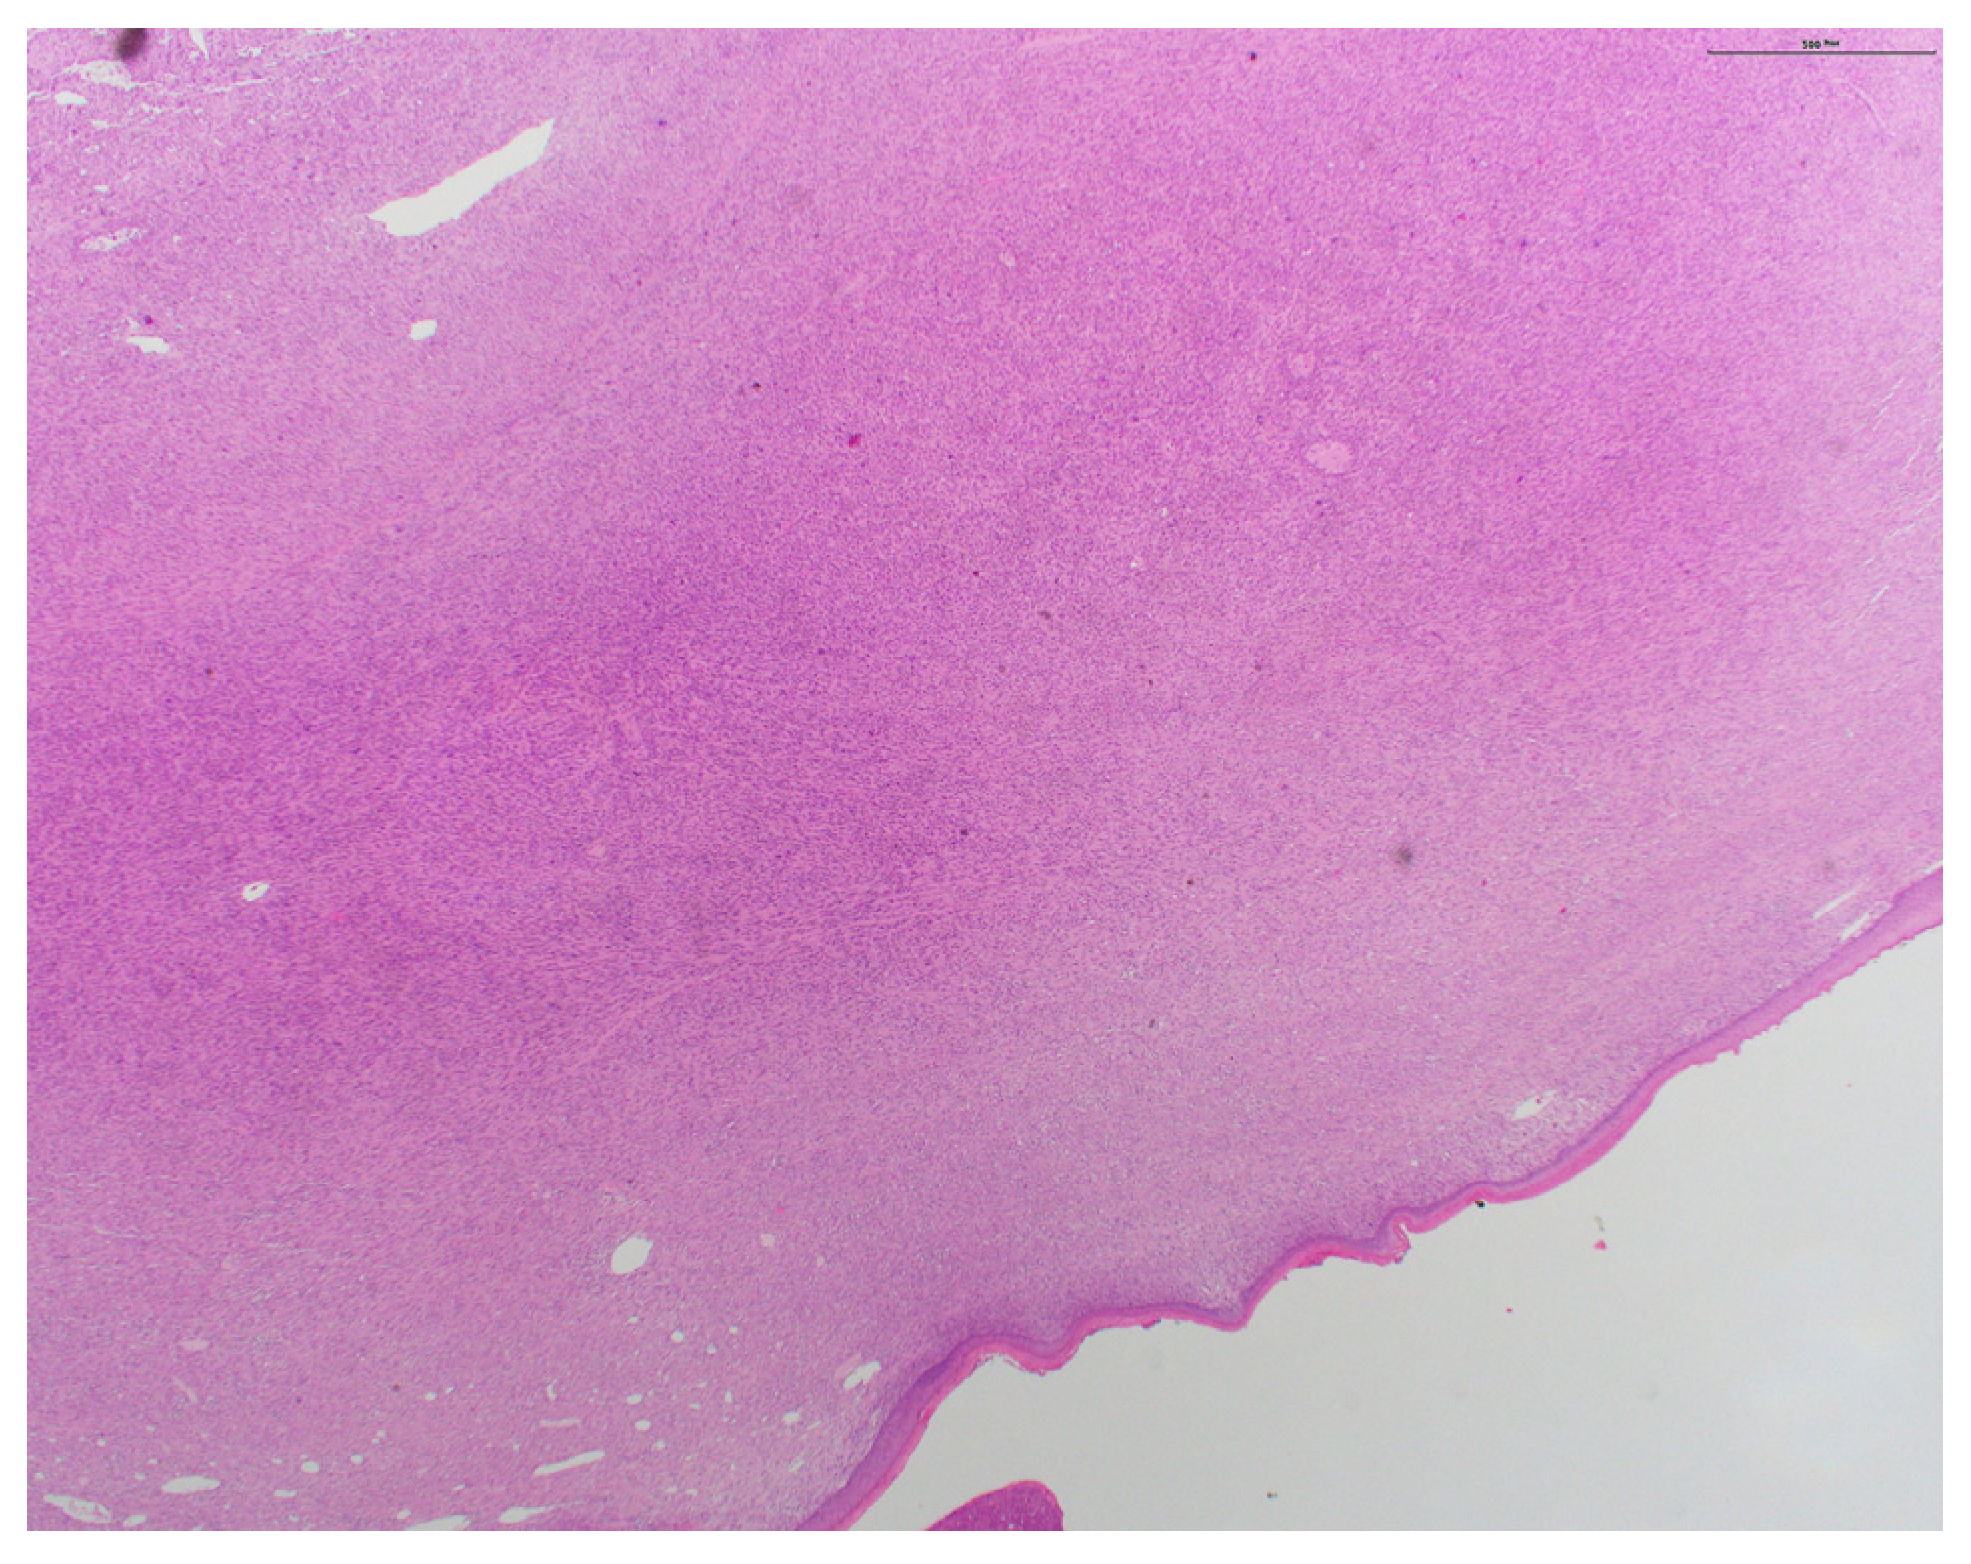

A Case of Pleomorphic Dermal Sarcoma: Giant Exophytic Tumor of the Medial Canthus

2. Case Presentation